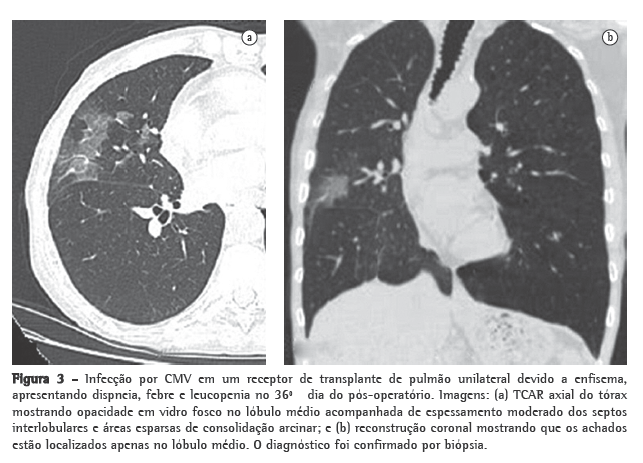

Infecções oportunistas ocorrem em 34-59% dos receptores de transplante de pulmão.(13) Infelizmente, em pacientes com nova pneumonia oportunista, os achados de radiografia de tórax podem ser normais, e achados anormais, quando presentes, são frequentemente ­inespecíficos.(11) O citomegalovírus (CMV) é a infecção oportunista mais frequente entre tais pacientes.(14) A incidência da infecção pelo CMV atinge seu pico entre 1 e 2 meses após o transplante, a maioria dos casos ocorrendo entre o 1º e o 12º mês do pós-operatório.(11,14) A infecção pelo CMV pode ser primária e secundária. A infecção primária ocorre em mais de 90% dos pacientes soronegativos para CMV recebendo um pulmão de um doador soropositivo para CMV e se torna grave em 50-60% de tais casos.(11) A infecção secundária resulta da exposição a uma cepa de CMV diferente ou da reativação de uma infecção latente no receptor, e normalmente é menos grave que a infecção primária.(11) As manifestações clínicas da infecção pelo CMV incluem dispneia, febre, mal-estar e leucopenia, apesar de muitos pacientes com pneumonia por CMV confirmada histologicamente serem assintomáticos.(15) O diagnóstico da pneumonia pelo CMV é tipicamente confirmado apenas após a lavagem broncoalveolar e biópsia transbrônquica. As manifestações radiológicas da pneumonia por CMV incluem, como demonstrado na Figura 3, opacidades em vidro fosco, espessamento dos septos interlobulares e consolidação, bem como opacidades reticulares difusas ou ­reticulonodulares, nódulos e pequenas áreas de derrame.(14)

Em receptores de transplante pulmonar com infecção por CMV ativa, os achados da radiografia de tórax podem ser normais.(11) As TCs têm melhor captura das manifestações radiológicas da infecção, que afeta o órgão quase exclusivamente. As manifestações mais frequentes da TC são opacidades em vidro fosco, opacidades do tipo árvore em brotamento, consolidação dos espaços aéreos, nódulos, espessamento dos septos interlobulares, derrames pleurais, espessamento/aumento da pleura e bronquiectasias.(11-15) Outros patógenos pulmonares frequentes que afetam esta população incluem herpes vírus, adenovírus e vírus respiratório sincicial.(11)